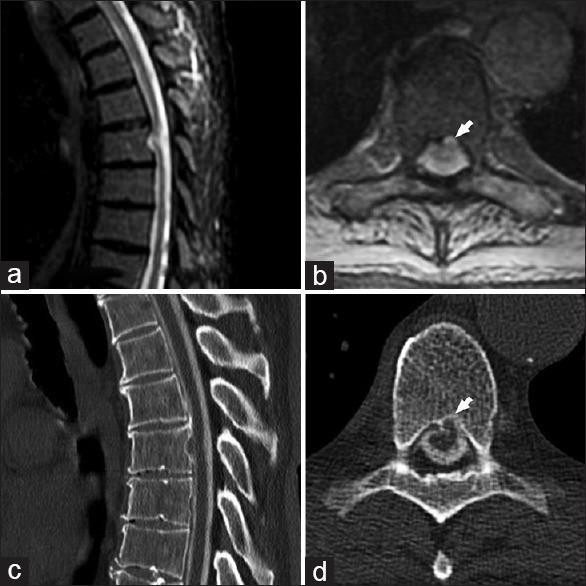

Idiopathic thoracic transdural intravertebral spinal cord herniation.

Idiopathic spinal cord herniation is a rare and often missed cause of thoracic myelopathy. The clinical presentation and radiological appearance is inconsistent and commonly confused with a dorsal arachnoid cyst and often is a misdiagnosed entity. While ventral spinal cord herniation through a dural defect has been previously described, intravertebral herniation is a distinct entity and extremely rare. We present the case of a 70-year old man with idiopathic thoracic transdural intravertebral spinal cord herniation and discuss the clinico-radiological presentation, pathophysiology and operative management along with a review the literature of this unusual entity.

特发性脊髓疝是一种罕见且常被漏诊的胸段脊髓病病因。其临床表现和影像学表现不一致,常与背侧蛛网膜囊肿相混淆,且往往是一个被误诊的疾病。虽然此前已有经硬脊膜缺损的腹侧脊髓疝的描述,但椎体内疝是一种独特的疾病,极为罕见。我们报告一例70岁男性特发性胸段经硬脊膜椎体内脊髓疝的病例,并讨论其临床影像学表现、病理生理学、手术治疗,同时回顾有关这一罕见疾病的文献。